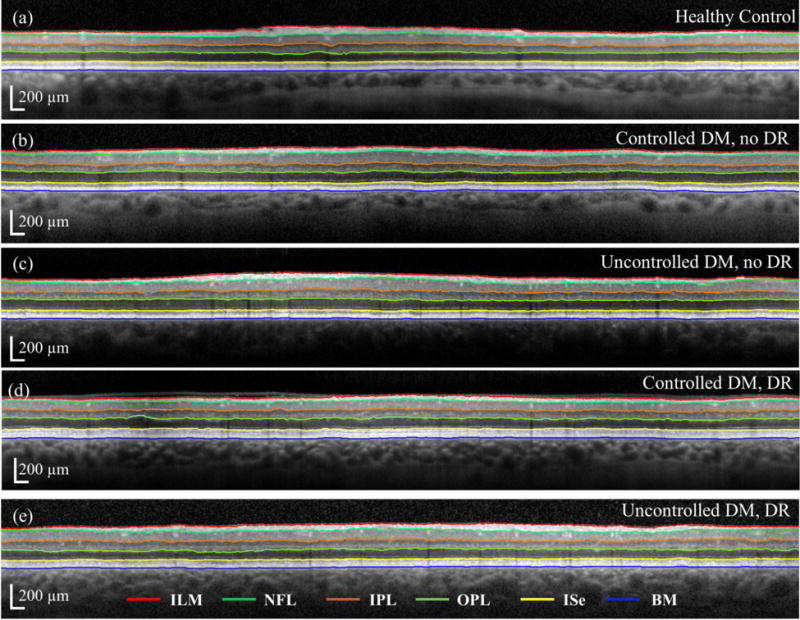

Six (6) retinal layer lines along: i) internal limiting membrane (ILM), ii) nerve fiber layer (NFL), iii) inner plexiform layer (IPL), iv) outer plexiform layer (OPL), v) inner segment ellipsoid (ISe) and vi) BM were automatically segmented using freely available open source code (Optical Coherence Tomography Segmentation and Evaluation GUI (OCTSEG), Pattern Recognition Lab, Friedrich-Alexander University, Erlangen-Nuremberg, Germany) developed based on research work on OCT[27]. We rarely corrected the segmented images manually, but did so when there was an obvious discontinuity in the automatic segmentation or existence of cystoid macular edema (CME). Figure 2(a) shows the flowchart of the presented method, and Fig. 2(b) shows representative segmented retinal layers in the OCT image. The red, light green, orange, dark green, yellow, and blue lines represent the ILM, NFL, IPL, OPL, ISe and BM, respectively. Figure 3 shows segmented retinal layer boundaries of the OCT images for a) Gr 1; b) Gr 2; c) Gr 3; d) Gr 4; and e) Gr 5, respectively, shown in Fig. 1. The OCTSEG software generates a metadata file containing the retinal layer thicknesses at each A-scan location, which was then read and processed in MATLAB™ to prepare the tables for analysis of variance (ANOVA).

Figure 3.

Segmented retinal layers of the OCT images for a) healthy control; b) controlled DM, no DR; c) uncontrolled DM, no DR; d) controlled DM, DR; and e) uncontrolled DM, DR groups, respectively, shown in Fig. 1. The red, light green, orange, dark green, yellow and blue lines correspond to those specified in Fig. 2 caption.